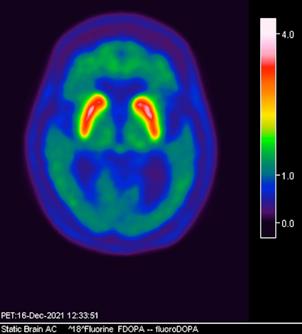

Figura 3. Reconstrucción mediante imagen molecular de imagen híbrida PET-RM 3T con 6-[18F] FDOPA observando disminución de la captación del radiotrazador a nivel de ambos putámenes en la región posterior, media y anterior así como en ambos núcleos ca dados de predominio derecho.

Figura 4. Reconstrucción mediante imagen molecular de imagen híbrida PET-RM 3T con 6-[18F]FDOPA observando captación adecuada y conservada del radiotrazador en el cuerpo estriado (ambos putámenes y núcleos caudados) en un paciente negativo para enfermedad de parkinson.